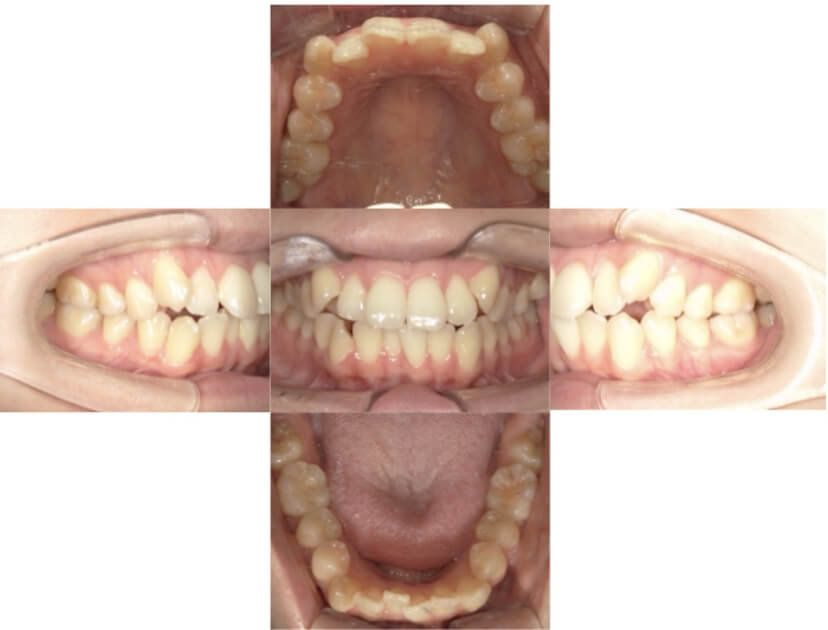

症例1

上顎前突、叢生

抜歯

ブラケット矯正

上下顎叢生、上顎前突(出っ歯、上下の前歯のガタガタ)のケースです。

装置はラビアル(上下表側)で、上顎の小臼歯を2本抜歯を行っています。抜歯したスペースを使って、上の前歯の後方移動と叢生(ガタガタ)と出っ歯の改善を行っています。下は歯と歯の間にIPR(隣接面削合)を行い、スペースを確保し、叢生の改善を行っています。

主訴 前歯のガタガタと出っ歯が気になる。

年齢・性別 47歳 女性

お住まいの地域 神奈川県川崎市

治療方針 抜歯スペースおよびIPRを利用して上前歯の叢生(ガタガタ)の改善

抜歯部位 上顎左右第一小臼歯

使用装置 ラビアル(上下表側)、顎間ゴム

治療期間 2年0か月

治療回数 15回

リテーナー クリアリテーナー

BEFORE

AFTER